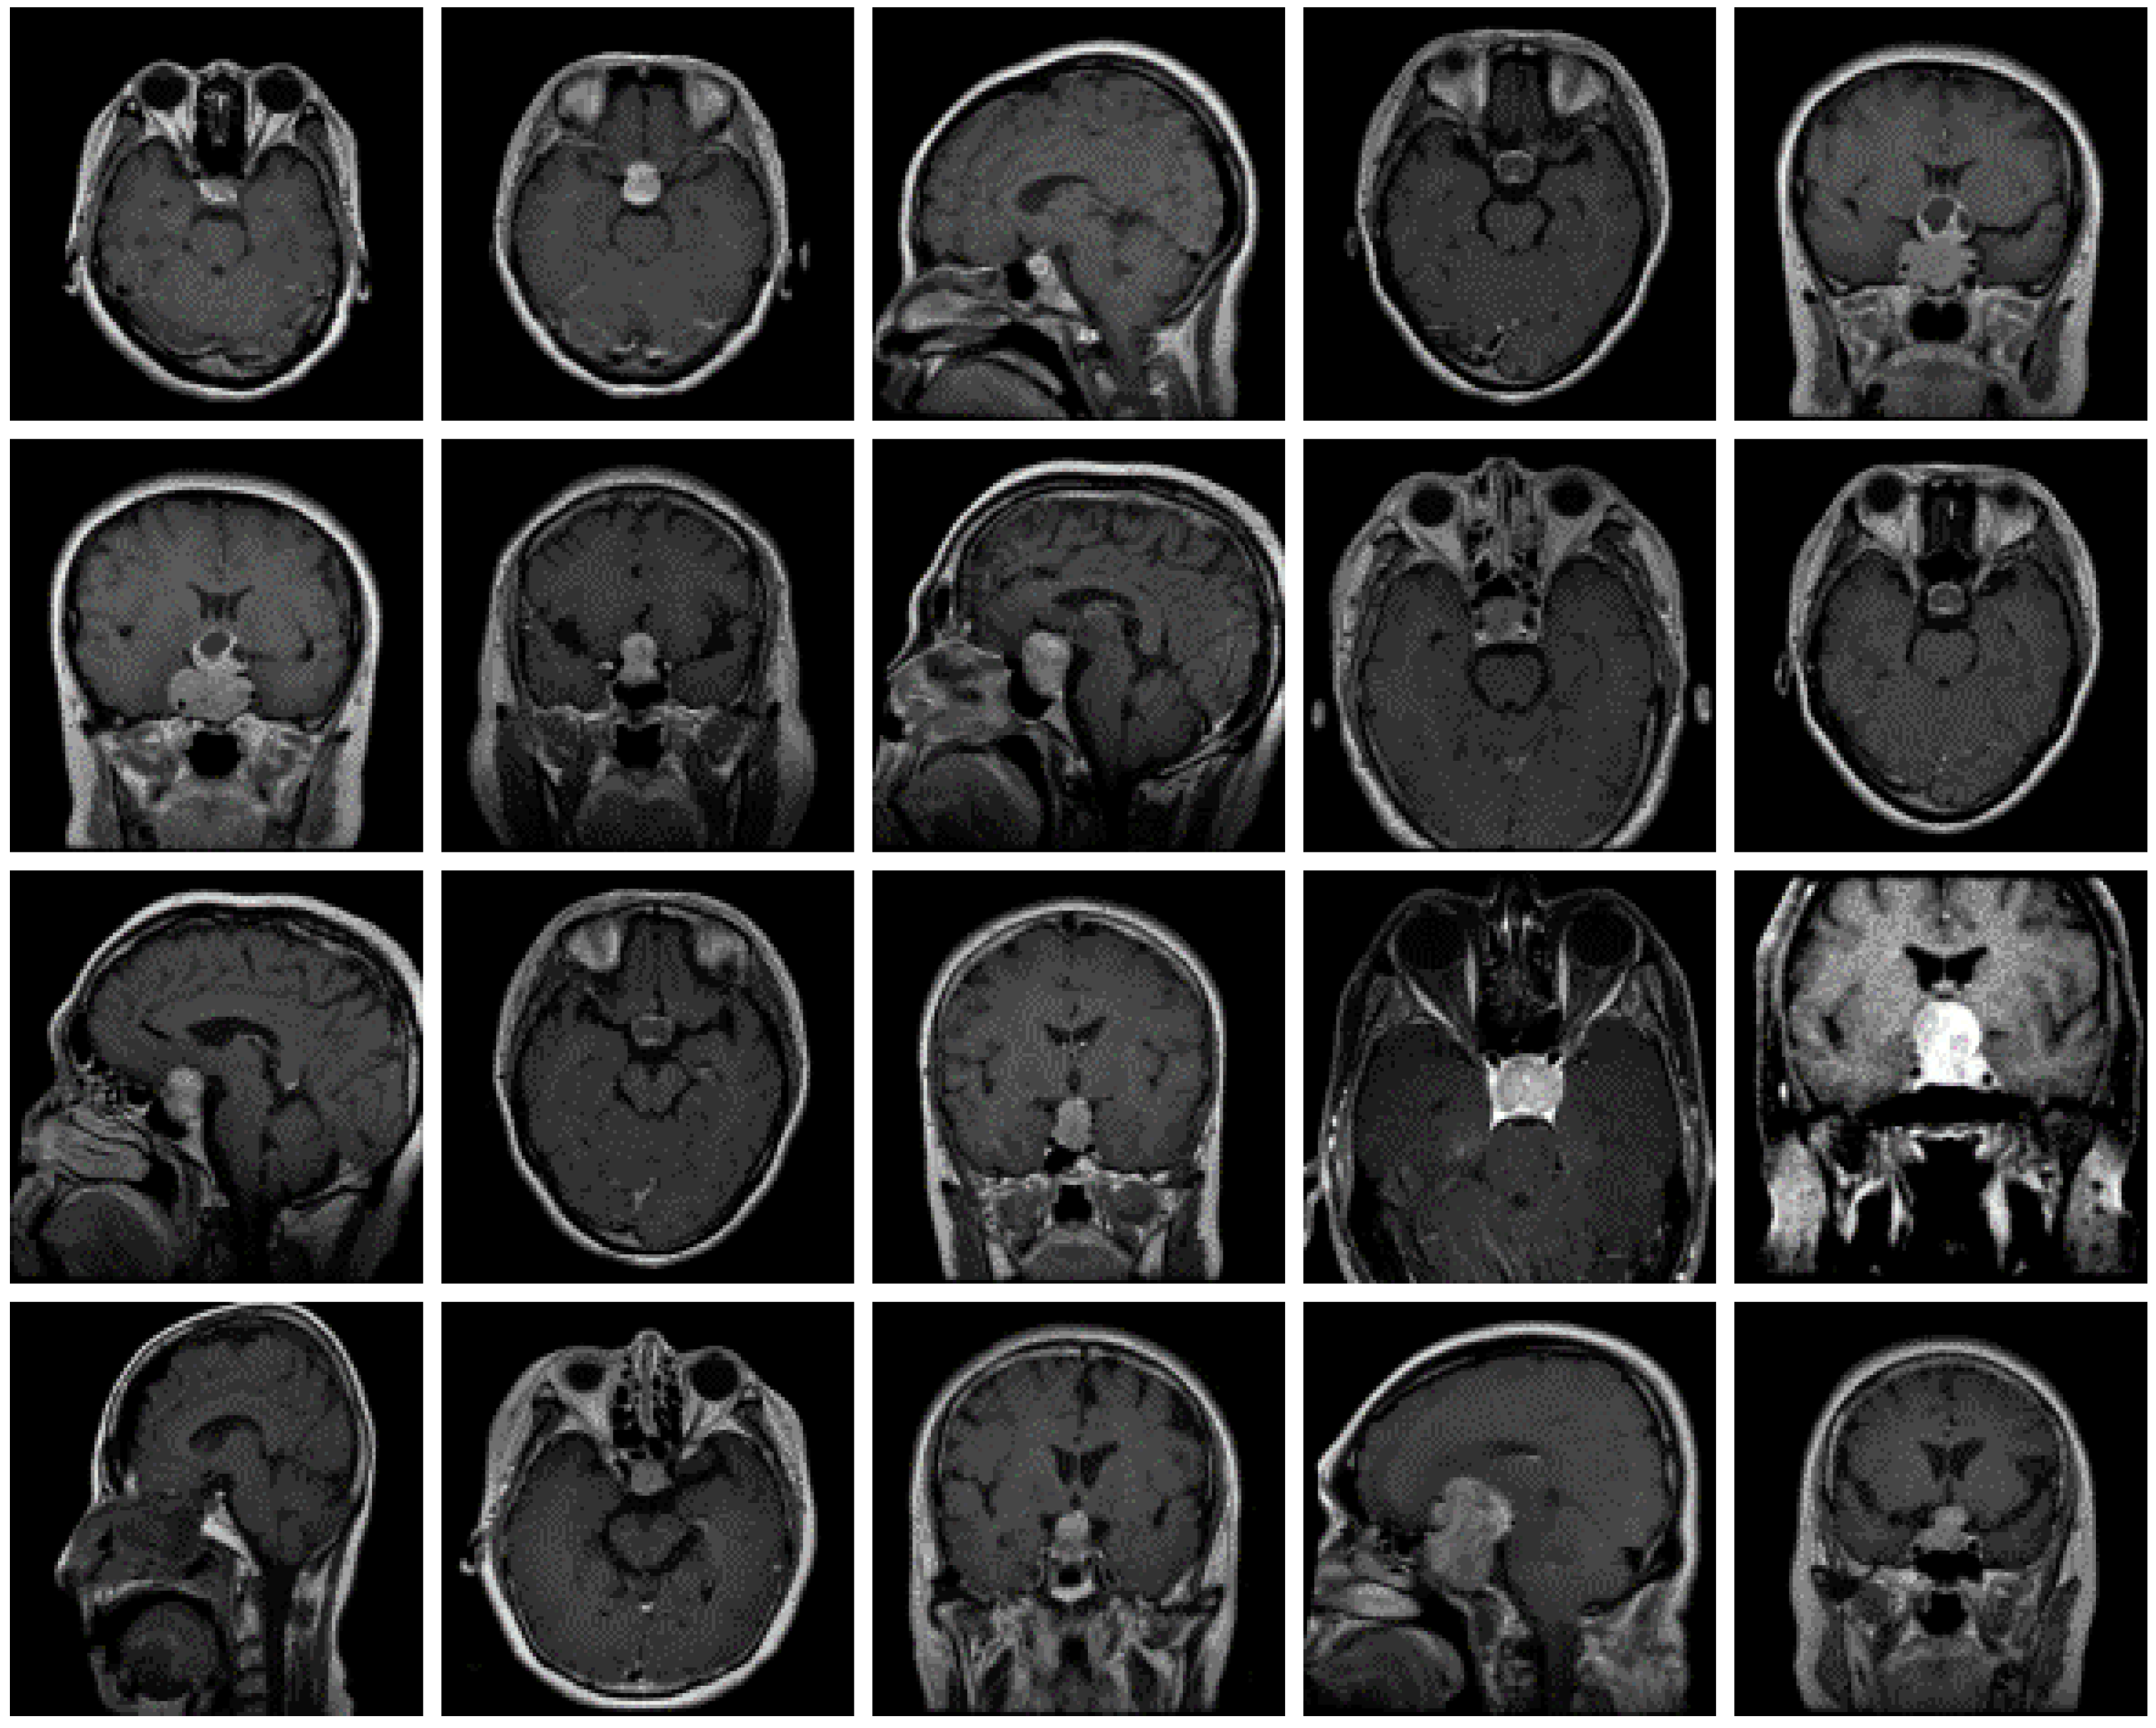

The dataset used for this current work is compiled from three other datasets: Figshare, SARTAJ, and Br35h. This composite dataset contains 2880 T1- weighted contrast-enhanced MRI brain images [26]. Gadolinium was used as contrast agent in these images. The target dataset has 829 images for glioma tumor, 825 images for meningioma tumor, 830 images for pituitary tumor and 396 images for no tumor cases. The images of the target dataset have a resolution of 512 × 512 × 3 with 24 bits color depth. Figure 1, Figure 2, Figure 3 and Figure 4 show some examples for each possible class: no tumor, glioma, meningioma, and pituitary tumor, respectively. The target dataset is split with 70% used for training and the remaining 30% kept aside for estimating the validation accuracy.

Figure 4.

Examples of MRI scans of pituitary tumors.